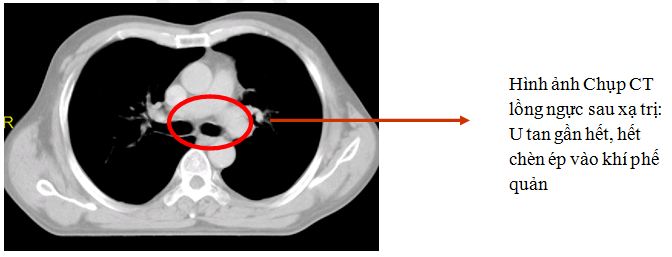

Kết quả :

Bệnh nhân đỡ khó thở ngay sau khi xạ trị 1 buổi, không phải thở O2

Sau 10 buổi, tự đi lại tốt, sinh hoạt gần như bình thường

|

| Hình ảnh bệnh nhân sau điều trị: hết khó thở, bệnh nhân tự đi lại sinh hoạt bình thường |